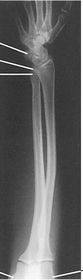

| AP Forearm | not AP - wrist is internally rotated, proximal radius and ulna are superimposed |

| Lateral Forearm | Elbow is not 90 degrees proximal radius and ulna are superimposed |

| AP Forearm | ANATOMY: entire forearm: wrist joint -> elbow joint CRITERIA: slight superimposition of proximal radius/ulna POSITIONING: CR perpendicular @ midforearm |

| Lateral Forearm | ANATOMY: entire forearm including wrist joint and elbow joint CRITERIA: humeral epicondyles must be superimposed distal radius/ulna superimposed half of radial head superimposed by coronoid process olecranon process in profile POSITIONING: CR perpendicular @ midforearm |